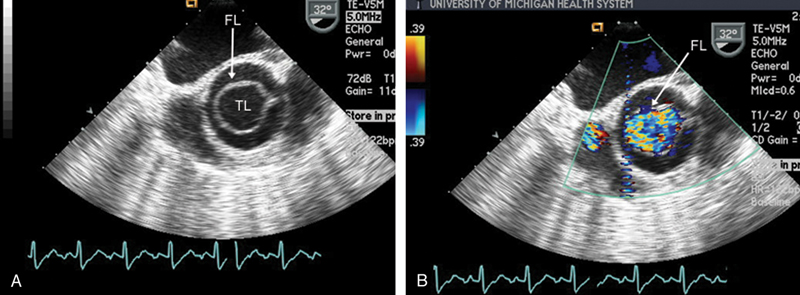

فحوصات تشخيصية لبعض امراض القلب والشرايين التاجية